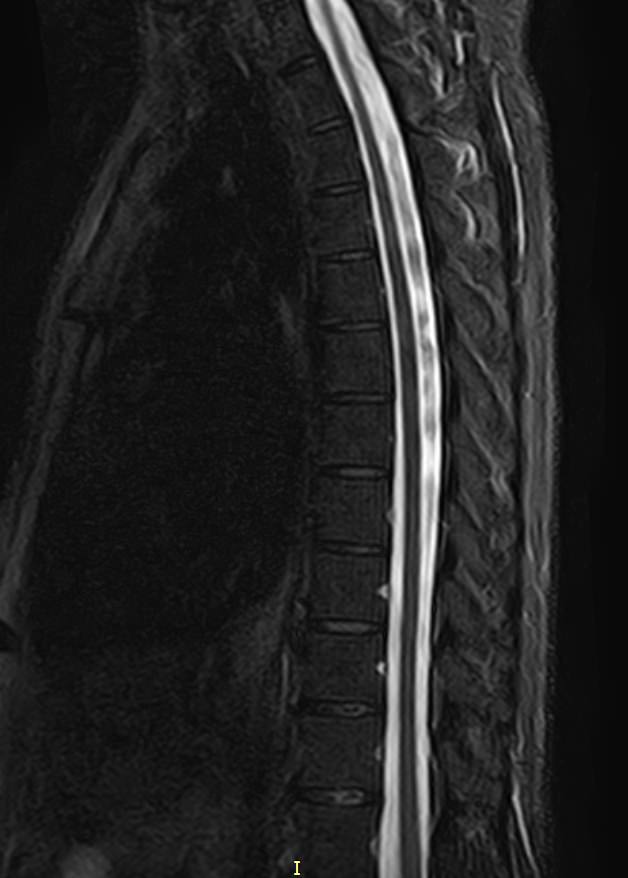

Магнитно-резонансная томография является наиболее чувствительным и эффективным методом диагностики дегенеративно-дистрофических заболеваний, травматических, воспалительных изменений, а также опухолевых процессов позвоночника. Метод позволяет оценить состояние структур позвонков, позвоночного канала с расположенным в нем спинным мозгом и окружающих мягких тканей, кроме того является основным способом диагностики демиелинизирующих заболеваний спинного мозга.

В клинике Доступная медицина установлен новейший высокопольный томограф экспертного класса TOSHIBA VANTAGE TITAN 1,5 Тесла, на котором выполняется комплексное обследование позвоночника. За счет высокой напряженности магнитного поля аппарат при сканировании создает изображения на плоскости превосходной четкости, затем с помощью компьютерных приложений данные преобразуются в изображения трехмерного формата, что обеспечивает точность и достоверность диагностики.

При подозрении на распространенный процесс с поражением различных уровней позвоночника в клинике «Доступная медицина» возможно проведение комплексной МРТ позвоночника – 3 отдела.

Комплексная МРТ позвоночника в большинстве случаев проводится в стандартном режиме без использования контраста, но для улучшения визуализации патологических очагов в некоторых случаях может понадобиться введение контрастного вещества. Для контрастирования применяется препарат на основе солей гадолиния, который полностью удаляется из организма в течение последующих суток.